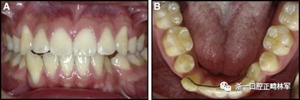

臨床檢查顯示固定保持器完好,弓絲沒有斷裂(圖13)。在下頜右側中切牙唇側和鄰近側切牙的舌側注意到有牙齦退縮。這些牙齒在退縮方向上存在顯著的扭矩差異。下頜的左側尖牙頰側錯位,而右側尖牙舌側傾斜。三維射線照片證實了下頜右側尖牙面側牙槽骨喪失,右側中切牙的喪失程度較輕。右側側切牙根也從舌側骨面上扭轉出來(圖14)。

正畸文獻閱讀--固定舌側保持器作用下意外的牙齒移動

圖13.粘合到尖牙和切牙上的柔性螺旋弓絲保持器,伴有牙齦退縮和附著喪失,中切牙之間嚴重的扭矩差異以及兩顆尖牙的橫向移動和扭矩。牙周問題和牙齒移動的嚴重程度均為牙周正畸聯合治療的指征:A,正面視圖; B,咬合面視圖。